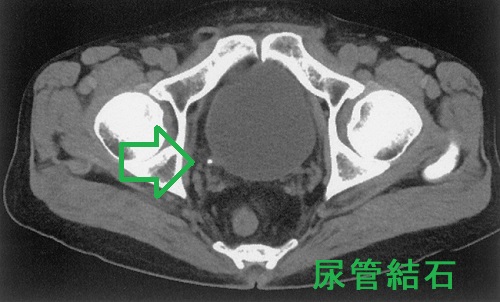

- 過剰な血清カルシウムが腎結石(腎臓結石)・尿路結石を形成し腎不全

原発性副甲状腺機能亢進症の約4%に、高カルシウム血症による腎結石(腎臓結石): 内分泌尿路結石を認めます[Urolithiasis. 2018 Oct;46(5):453-457.][J Clin Endocrinol Metab. 2011 Aug;96(8):2377-85.]。

再発性あるいは多発性(散在性)尿路結石患者の12.6%が原発性副甲状腺機能亢進症とされます(泌尿器科紀要 (1984), 30(7): 975-979)。

原発性副甲状腺機能亢進症の腎結石(腎臓結石): 内分泌尿路結石はリン酸カルシウム結石です。[JAMA Surg. 2020 Sep 1;155(9):861-868.]